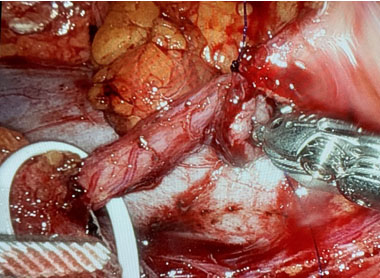

A 34-year-old male was referred for incidental right hydronephrosis observed on a CT abdomen and pelvis after a motor vehicle collision. The patient reported right flank pain following the accident. Past medical history and past surgical history were unremarkable. The patient denied hematuria, dysuria, lower urinary tract symptoms, or a history of urinary tract infections. Right costovertebral angle tenderness was present on physical examination. Urinalysis and urine culture were negative. Serum creatinine was 1.17 mg/dL, down from a previous measurement months before the motor vehicle accident of 1.77 mg/dL. A CT urogram revealed severe right hydronephrosis with possible ureteropelvic junction obstruction and diffuse thinning of the right renal parenchyma (Figure 1A and Figure 1B). A diuretic renogram was then obtained due to the thinning of the renal parenchyma and an unknown duration of hydronephrosis on the right kidney. There was a concern that the renal function may have declined over time due to prolonged obstruction. Subsequent diuretic nuclear renogram demonstrated normal uptake and a dilated right renal collecting system with delayed response to Lasix consistent with right partial high-grade obstruction (t1/2 25 minutes) (Figure 2). We then proceeded with cystoscopy with right retrograde pyelography to better detail the origin of the obstructive process. This demonstrated a tortuous proximal ureter with medial deviation and severe hydronephrosis consistent with a retrocaval ureter (Figure 3). The additional investigation using a retrograde pyelogram was performed for better diagnostic testing in case of future intraoperative planning for correction of the ureter. The retrograde pyelogram added details on the course of the proximal ureter and its’ anatomical tortuosity. A ureteral stent was placed for symptomatic relief of obstruction. The patient elected to undergo right robotic-assisted laparoscopic ureteroureterostomy. The patient was given prophylactic antibiotics. He was placed in the left lateral decubitus position with table flexion. Standard 8 mm da Vinci Xi (Intuitive Surgical, Sunnyvale, CA) trocar placement was performed for a right renal procedure (Figure 4). The robotic portion began with medial reflection the hepatic flexure and exposure of the right renal pelvis in standard fashion. The renal pelvis was expectedly dilated and prominent. The proximal ureter and IVC were identified. The ureteropelvic junction was dissected and encircled with a vessel loop. The ureter was found to be coursing posterior to the IVC, confirming retrocaval ureter. Identification of the ureter distal to the level of obstruction on the medial side of the IVC in the interaortocaval space was conducted (Figure 5). The distal aspect of the ureter was isolated with a second vessel loop. Care was taken not to unduly devascularize the ureter while mobilizing it to the extent allowing for transection and transposition of the ureter ventral to the IVC. The proximal ureter was sharply transected just distal to the ureteropelvic junction. The previously placed ureteral stent was removed. The ureter was transposed anterior to the IVC without tension (Figure 6). The proximal and distal ends of the ureter were spatulated, and a standard ureteroureterostomy was performed with two running stitches of 4-0 PDS suture (Ethicon, Bridgewater, NJ). Prior to completion of the ureteral anastomosis, a new 6 French, 28 cm double-J ureteral stent was then advanced antegrade over a Sensor wire (Boston Scientific, Marlborough, MA). The proximal stent coil was placed into the renal pelvis, and the anastomosis was completed. A JP drain was placed, and a Foley catheter was kept indwelling.

Figure 6: Transposed ureter after previous ureteral stent was removed without signs of tension.

Share Image: